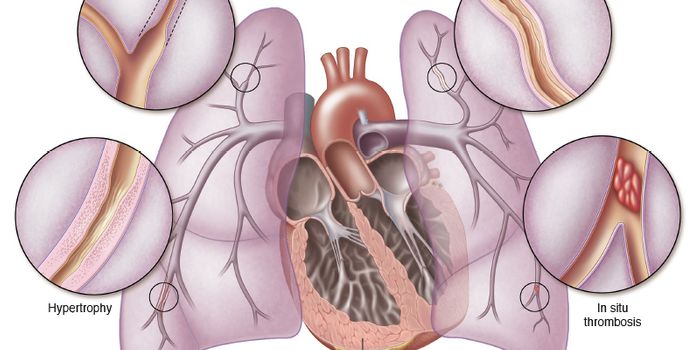

FEB 17, 2016CardiologySildenafil is a drug infamous for treating erectile dysfunction, but a new study shows that the same blood vessel dilati ...

DEC 05, 2015CardiologyThe results of a new study published online this week in the Journal of the American College of Cardiology: Heart Failur ...

DEC 28, 2017CardiologyKey differences between two cardiovascular conditions call for drugs with different therapeutic activity to successfully ...

JAN 16, 2016CardiologyPulmonary arterial hypertension (PAH), a disease without a cure that a thousand new Americans every year, requires numer ...

MAY 05, 2016CardiologyDilated cardiomyopathy (DCM) and hypertrophic cardiomyopathy (DCM) share some qualities in their tissue makeup and in th ...